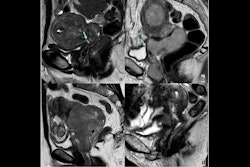

PI-RADS v2.1 shows high sensitivity for categorizing clinically significant prostate cancer on MRI at both the patient and lesion levels, according to an article published on 15 October in the American Journal of Roentgenology.

But "estimates of outcome metrics for PI-RADS version 2.1 have shown substantial heterogeneity, possibly relating to risks of bias in the relevant literature," the study authors explained. To assess the quality of the literature on this topic, they searched seven databases and registers for research published between March 2019 and September 2023 that reported diagnostic test accuracy metrics and/or cancer detection rates of PI-RADS v2.1 for identifying clinically significant prostate cancer in men suspected to have the disease.

The analysis included 117 studies with 25,228 patients and 15,553 lesions. The group used the QUADAS-2 tool to rate the studies' risk of bias and concerns of applicability. (QUADAS-2 assesses the quality of studies by evaluating research domains such as patient selection, the new procedure or protocol being investigated and its reference standard, and how and when tests/protocols were administered to study participants). It also calculated estimates of sensitivity and specificity of PI-RADS categories.